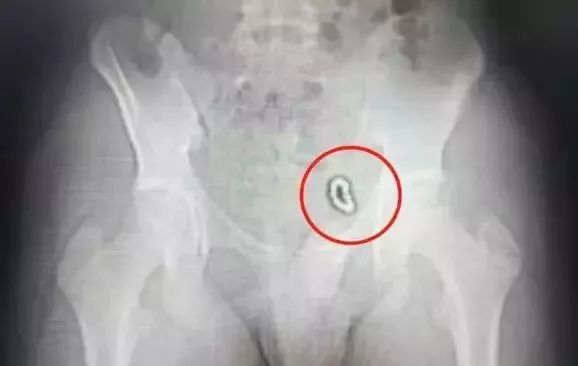

2018年11月,深圳13岁男童小浩被爸妈带到深圳市儿童医院泌尿外科门诊后,医生询问才知,小浩一年半前往自己的“小鸡鸡”里塞过小磁球,而且塞了10多个!

拍完X光片后发现:小浩下腹部左侧像是挂了一道环形“手串”,10多颗珠子紧紧连在一起,固定在膀胱左侧壁。